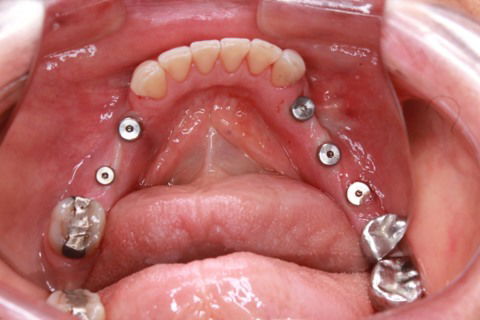

Implantes instalados

Cicatrizadores em posição

Cirurgia guiada de Implantes - sem cortes , sem pontos , sem sangue. Instalação de 5 implantes na região posterior da mandíbula.